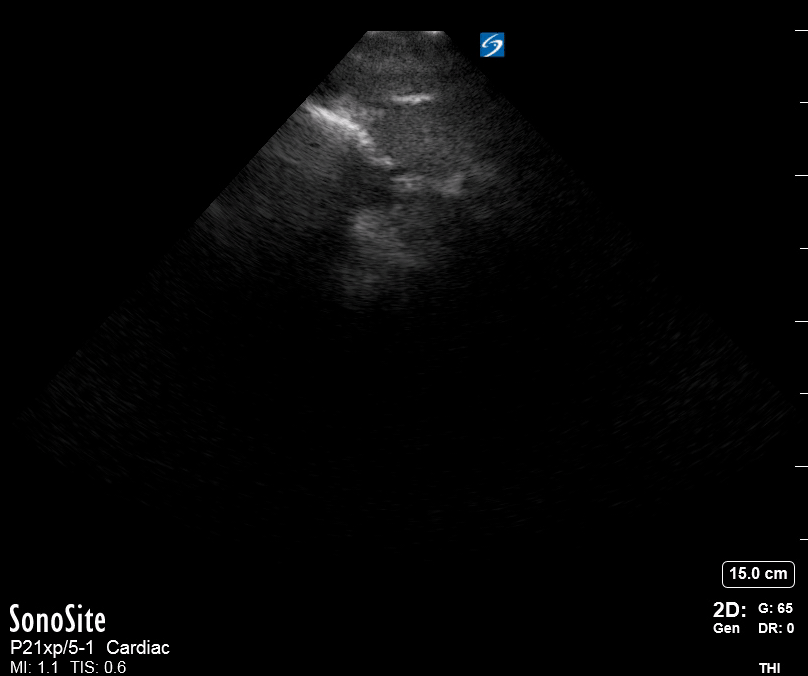

THE VIEWS

The PLAX view is best for exploring the aortic root. If performed by an experienced operator, aortic root measurements in this window correlate well with angio-CT measurements.

The Aortic root size varies with age and gender and should be measured at its widest point, perpendicular to its long axis. In general, a root > 4 cm should be considered borderline and enough to warrant a formal study.

Alternatively, the aortic root size can be estimated by the rule of thirds, where in the PLAx view the size of the RV, AoR, and LA should be roughly 1:1:1.

AORTIC DISSECTION

In both of these views, US may detect an intimal flap seen as a hyperechoic linear structure within the aortic lumen that moves with each heartbeat. The visualization of a flap carries a high specificity and should prompt immediate consultation with cardiothoracic surgery; however, ultrasound sensitivity for intimal flap is significantly low, and its absence does not rule out aortic dissection.